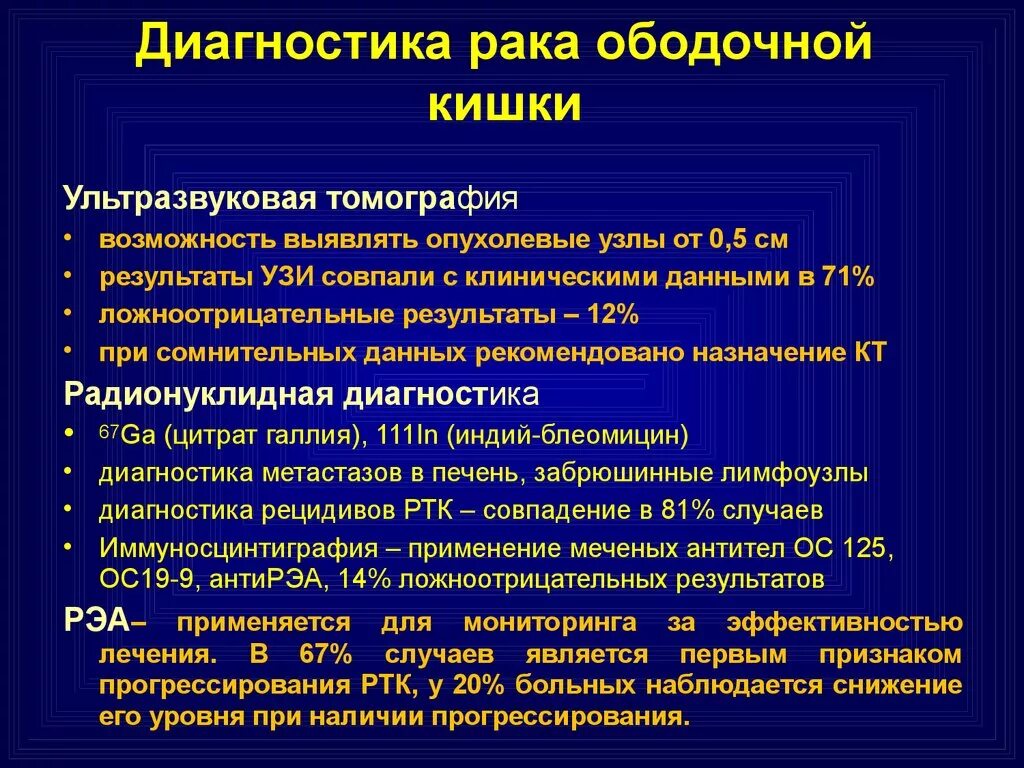

Гиповаскулярные метастазы печени кт. Опухоль желудка метастазирование. План обследования ободочной кишки. Диагноз опухоли ободочной кишки. Диагностические методы исследования ободочной кишки. Алгоритмы диагностики заболеваний толстой кишки.

План обследования ободочной кишки. Диагноз опухоли ободочной кишки. Диагностические методы исследования ободочной кишки. Алгоритмы диагностики заболеваний толстой кишки. Петрокливальная менингиома. Менингиома доброкачественная.